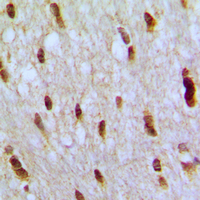

- Immunohistochemical analysis of NFAT5 staining in human brain formalin fixed paraffin embedded tissue section. The section was pre-treated using heat mediated antigen retrieval with sodium citrate buffer (pH 6.0). The section was then incubated with the antibody at room temperature and detected using an HRP conjugated compact polymer system. DAB was used as the chromogen. The section was then counterstained with hematoxylin and mounted with DPX.